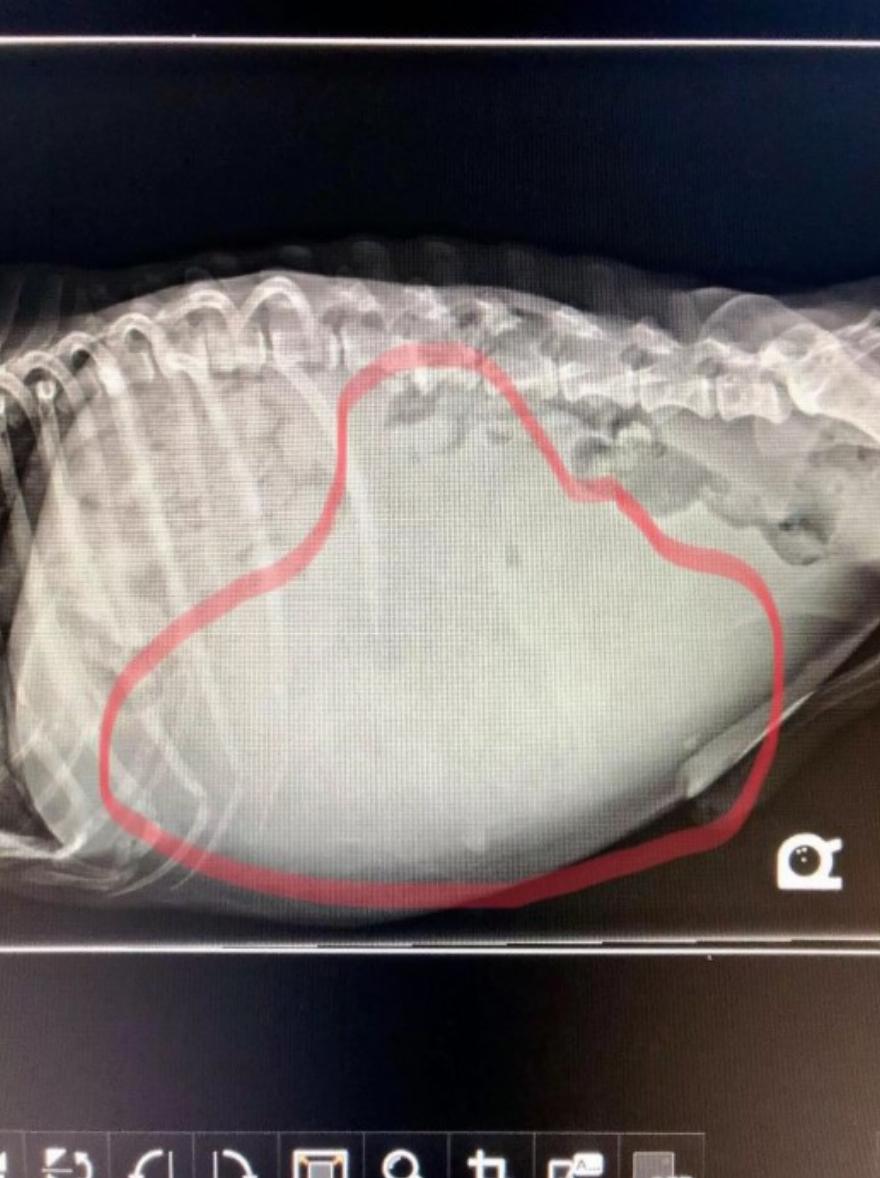

Σαν να μην έφταναν όλα αυτά για να τρομάξουν ένα φτωχό σκυλάκι, συν τοις άλλοις, οι άνθρωποι επρόκειτο να ανακαλύψουν ότι ο Holden είχε κάτι μέσα στο σώμα του που θα μπορούσε να τον σκοτώσει αργά.

Στον κτηνίατρο, οι ακτινογραφίες αποκάλυψαν έναν όγκο 7 κιλών που είχε σφηνωθεί στο σώμα του Holden, καθιστώντας τον δύσκολο ακόμη και να φάει οτιδήποτε.